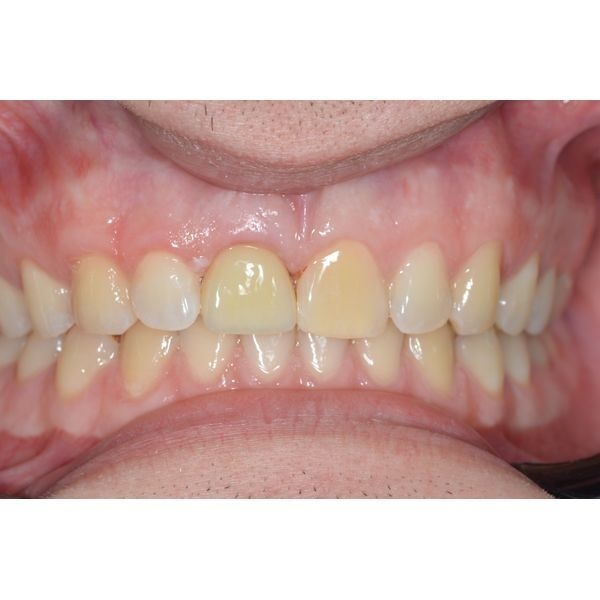

Через неделю после операции сняли швы. Спустя месяц провели контрольный осмотр. Протезирование запланировали примерно на 3–6-й месяц после хирургического вмешательства, точный срок зависел от приживления имплантата.

Пациент приходил на осмотр раз в месяц. Повторные КТ показывали, что имплантат приживался без осложнений.

С помощью немедленной имплантации пациенту восстановили переднюю часть зубного ряда.